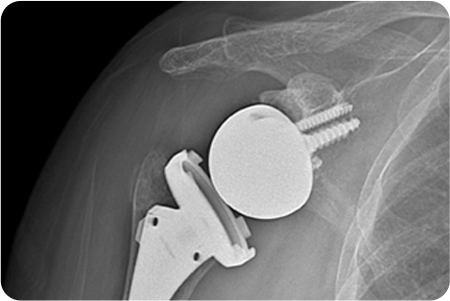

어깨 관절염

인공관절치환술

관절염으로 닳아버린 손상된 연골과 뼈를

정밀하게 절제합니다. 환자의 상태에 따라

전치환술/반치환술 중 선택하여 시행

합니다.